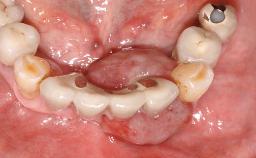

Management of a Technical Complication Caused by a Fractured Zirconia Abutment

A 24-year-old female patient was treated with an implant- supported crown for single-tooth replacement at site 11. A Straumann Bone Level RC implant (Institut Straumann AG, Basel, Switzerland) was placed with simultaneous bone augmentation, and the periimplant emergence profile was conditioned with a fixed implant-supported provisional crown. After finalization of the mucosal architecture, the clinical situation was transferred by means of a custom impression post for fabrication of an implant-supported screw-retained onepiece crown consisting of a CARES® zirconia abutment (Straumann) with a direct ceramic veneer.